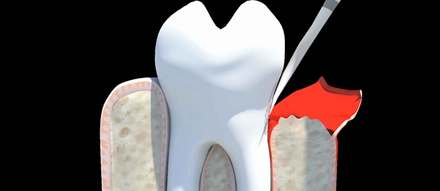

Flap surgery is a procedure where the gum flap is lifted away from the tooth. Diseased tissue and sometimes bone is removed.